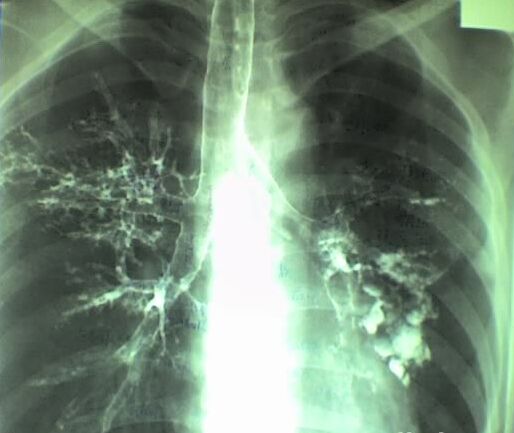

支气管扩张是哪些原因引起的?支气管扩张是大家都比较熟悉、对患者危害比较大的疾病,同样是支气管疾病中的一种,西安莲湖天颐堂中医医院曹文团专家介绍说:支气管扩张可发生于任何年龄,而症状却可能若干年后才出现,支气管扩张典型的症状即为慢性咳嗽、咳大量脓痰和反复咯血。那么引起支气管扩张的因素有哪些呢?

下一篇:支气管扩张有哪些症状